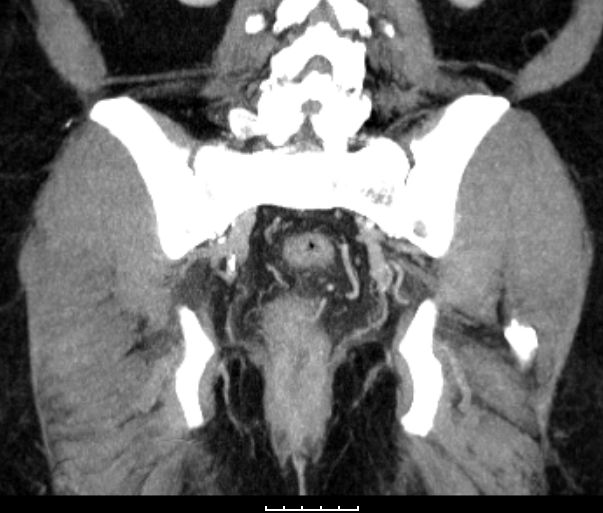

CT |

73-jährige Frau mit Stuhlverhalt und analer Blutung seit 5 Tagen. PE: Adenokarzinom des Analkanals. | ||